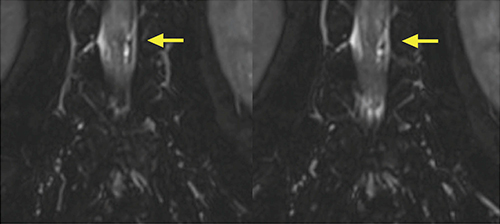

症例は71歳,男性。両下肢筋力低下と歩行困難による日常生活動作(ADL)低下を主訴に当院受診となった。既往歴として黄色靭帯骨化症・脊柱狭窄にて手術歴(胸髄・腰髄手術)があり,今回,脊髄MRIにて胸髄,腰仙髄の脊髄中心性髄内信号変化(硬膜動静脈瘻+,静脈うっ血性脊髄症s/o)を認め,MRIの脂肪抑制T2WIにてL1-2レベルの硬膜囊内左側寄りに,拡張,蛇行する脈管構造が疑われた(図1)。脊髄硬膜動静脈瘻(Dural AVF:以下,d-AVF)を見ている可能性があることから,確定診断を目的として3D-CTAの依頼となった。

図1 脂肪抑制T2WI